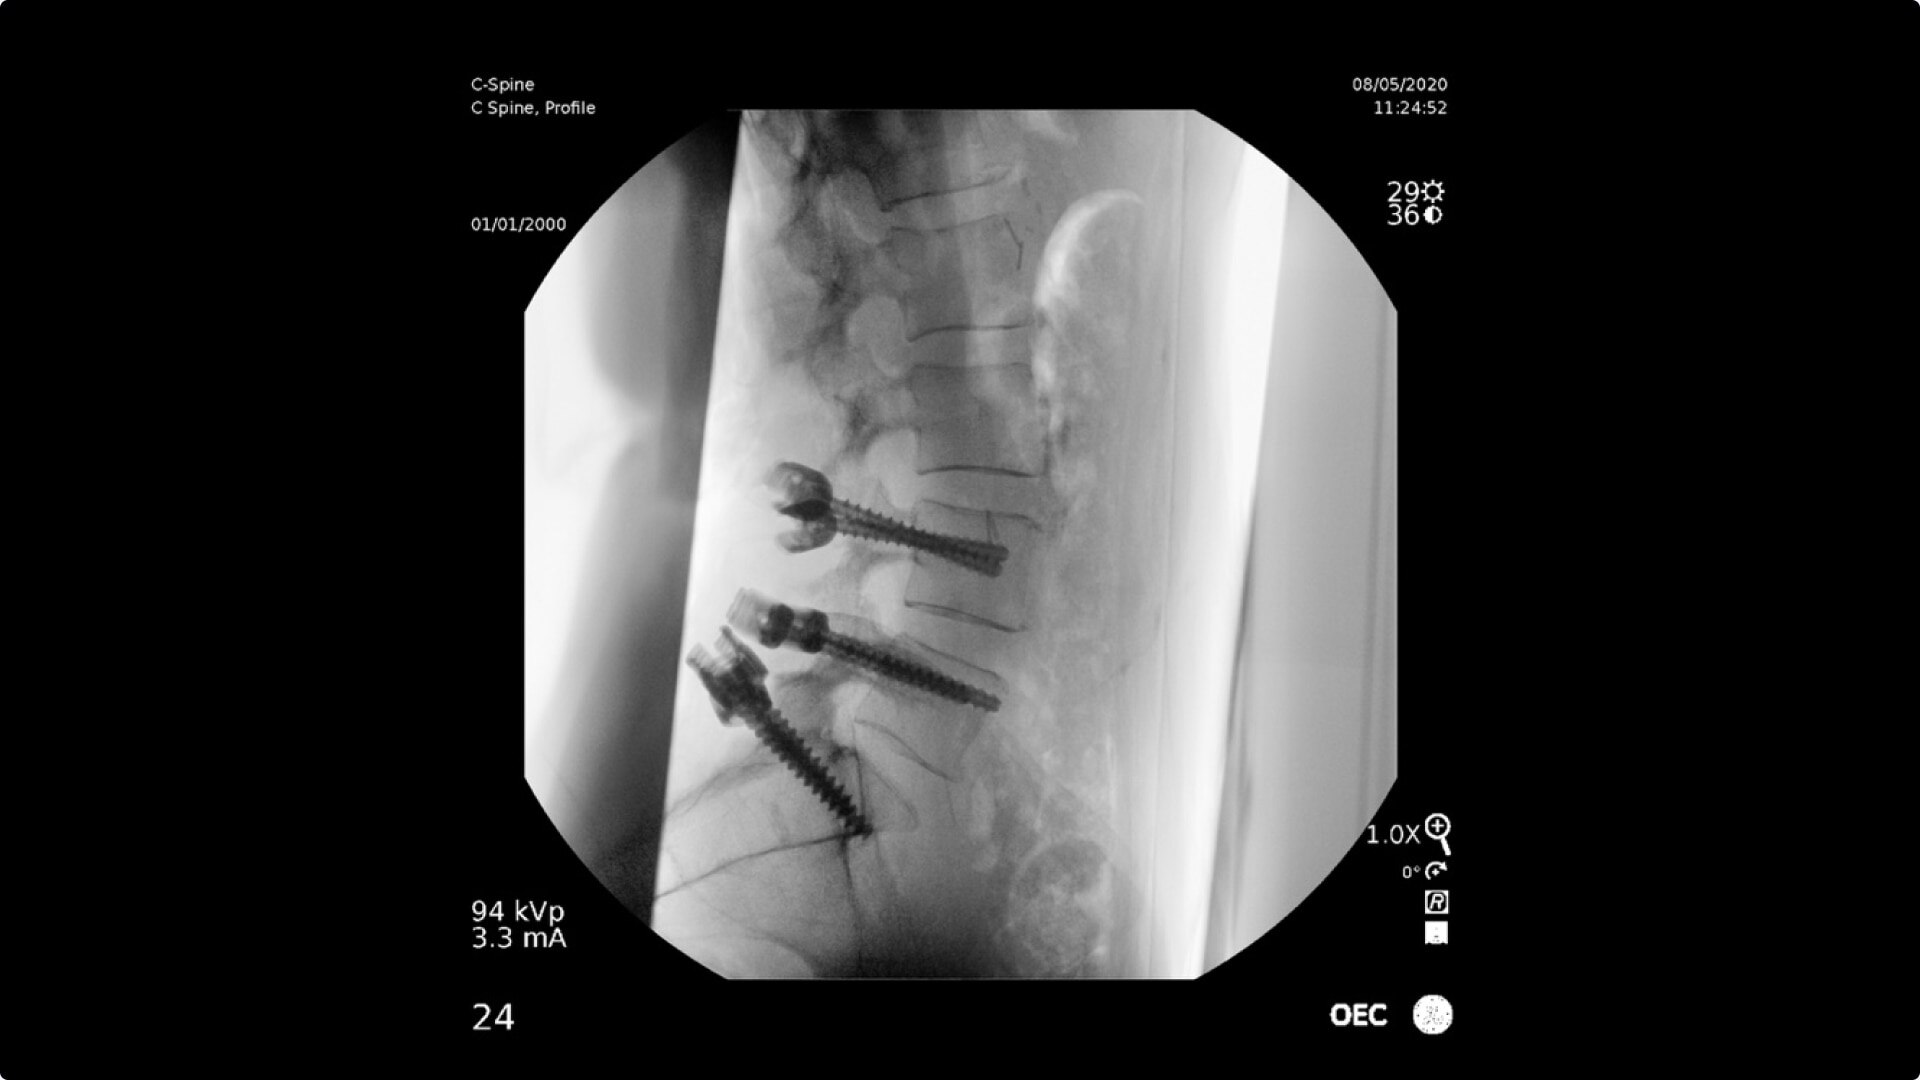

C-arms for Pain Management

Consistently experience amazing image quality, precision, and efficiency during simple to complex pain management procedures with OEC C-arms.

Achieve precision and efficiency while experiencing the image quality needed during simple to complex pain management procedures with OEC C-arms.

Pain management imaging you need

Pain Management procedures require powerful imaging systems.

OEC C-arms perform imaging in a variety of procedures such as:

• Thoracolumbar procedures